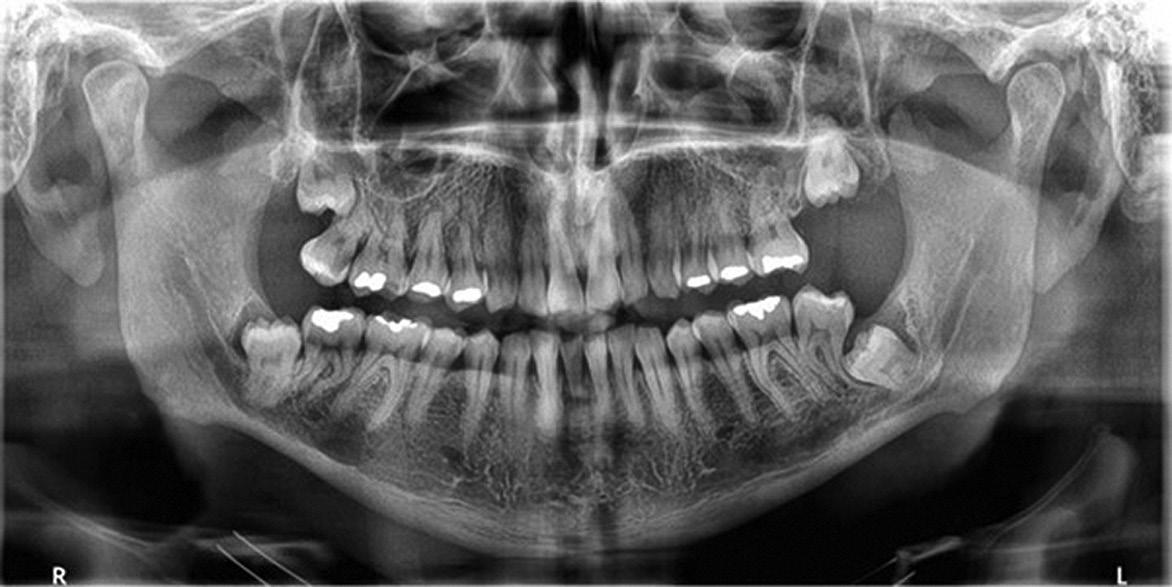

Clear radiographs are essential to accurate diagnosis and are a special test that dentists per form regularly many times throughout the day. Following the ALARA principle, we want to ensure we take a minimal number of radio graphs to ensure low radiation dosage so to repeat radiographs due to operator error should be avoided. The use of film holders allow the clinician to visualise how the radiographs should be taken to optimise the clarity of the image and ensure the diagnostic value of the image. Hawe Solutions x-ray film holders...

Figure 1: Radiographic Image of implants do not demonstrate bone loss due to the bisecting angle of the radiograph taken.

Figure 2: Radiographic image in a paralleling technique of implants dem onstrate moderate peri-implantitis with bone loss that will necessitate treatment.

• Allow exact posi tioning of the film or phosphor plate relative to the tooth - no bending and thus no distortion;

• Require no guesswork - exclusive, automatic reliance on the extraoral aiming and centring device;

• Deliver semi-reproducible images (quasi standardisation)the use of film holders allows some sense of reproducibility for assessment over time; and

• Produce optimally clear radiographs.